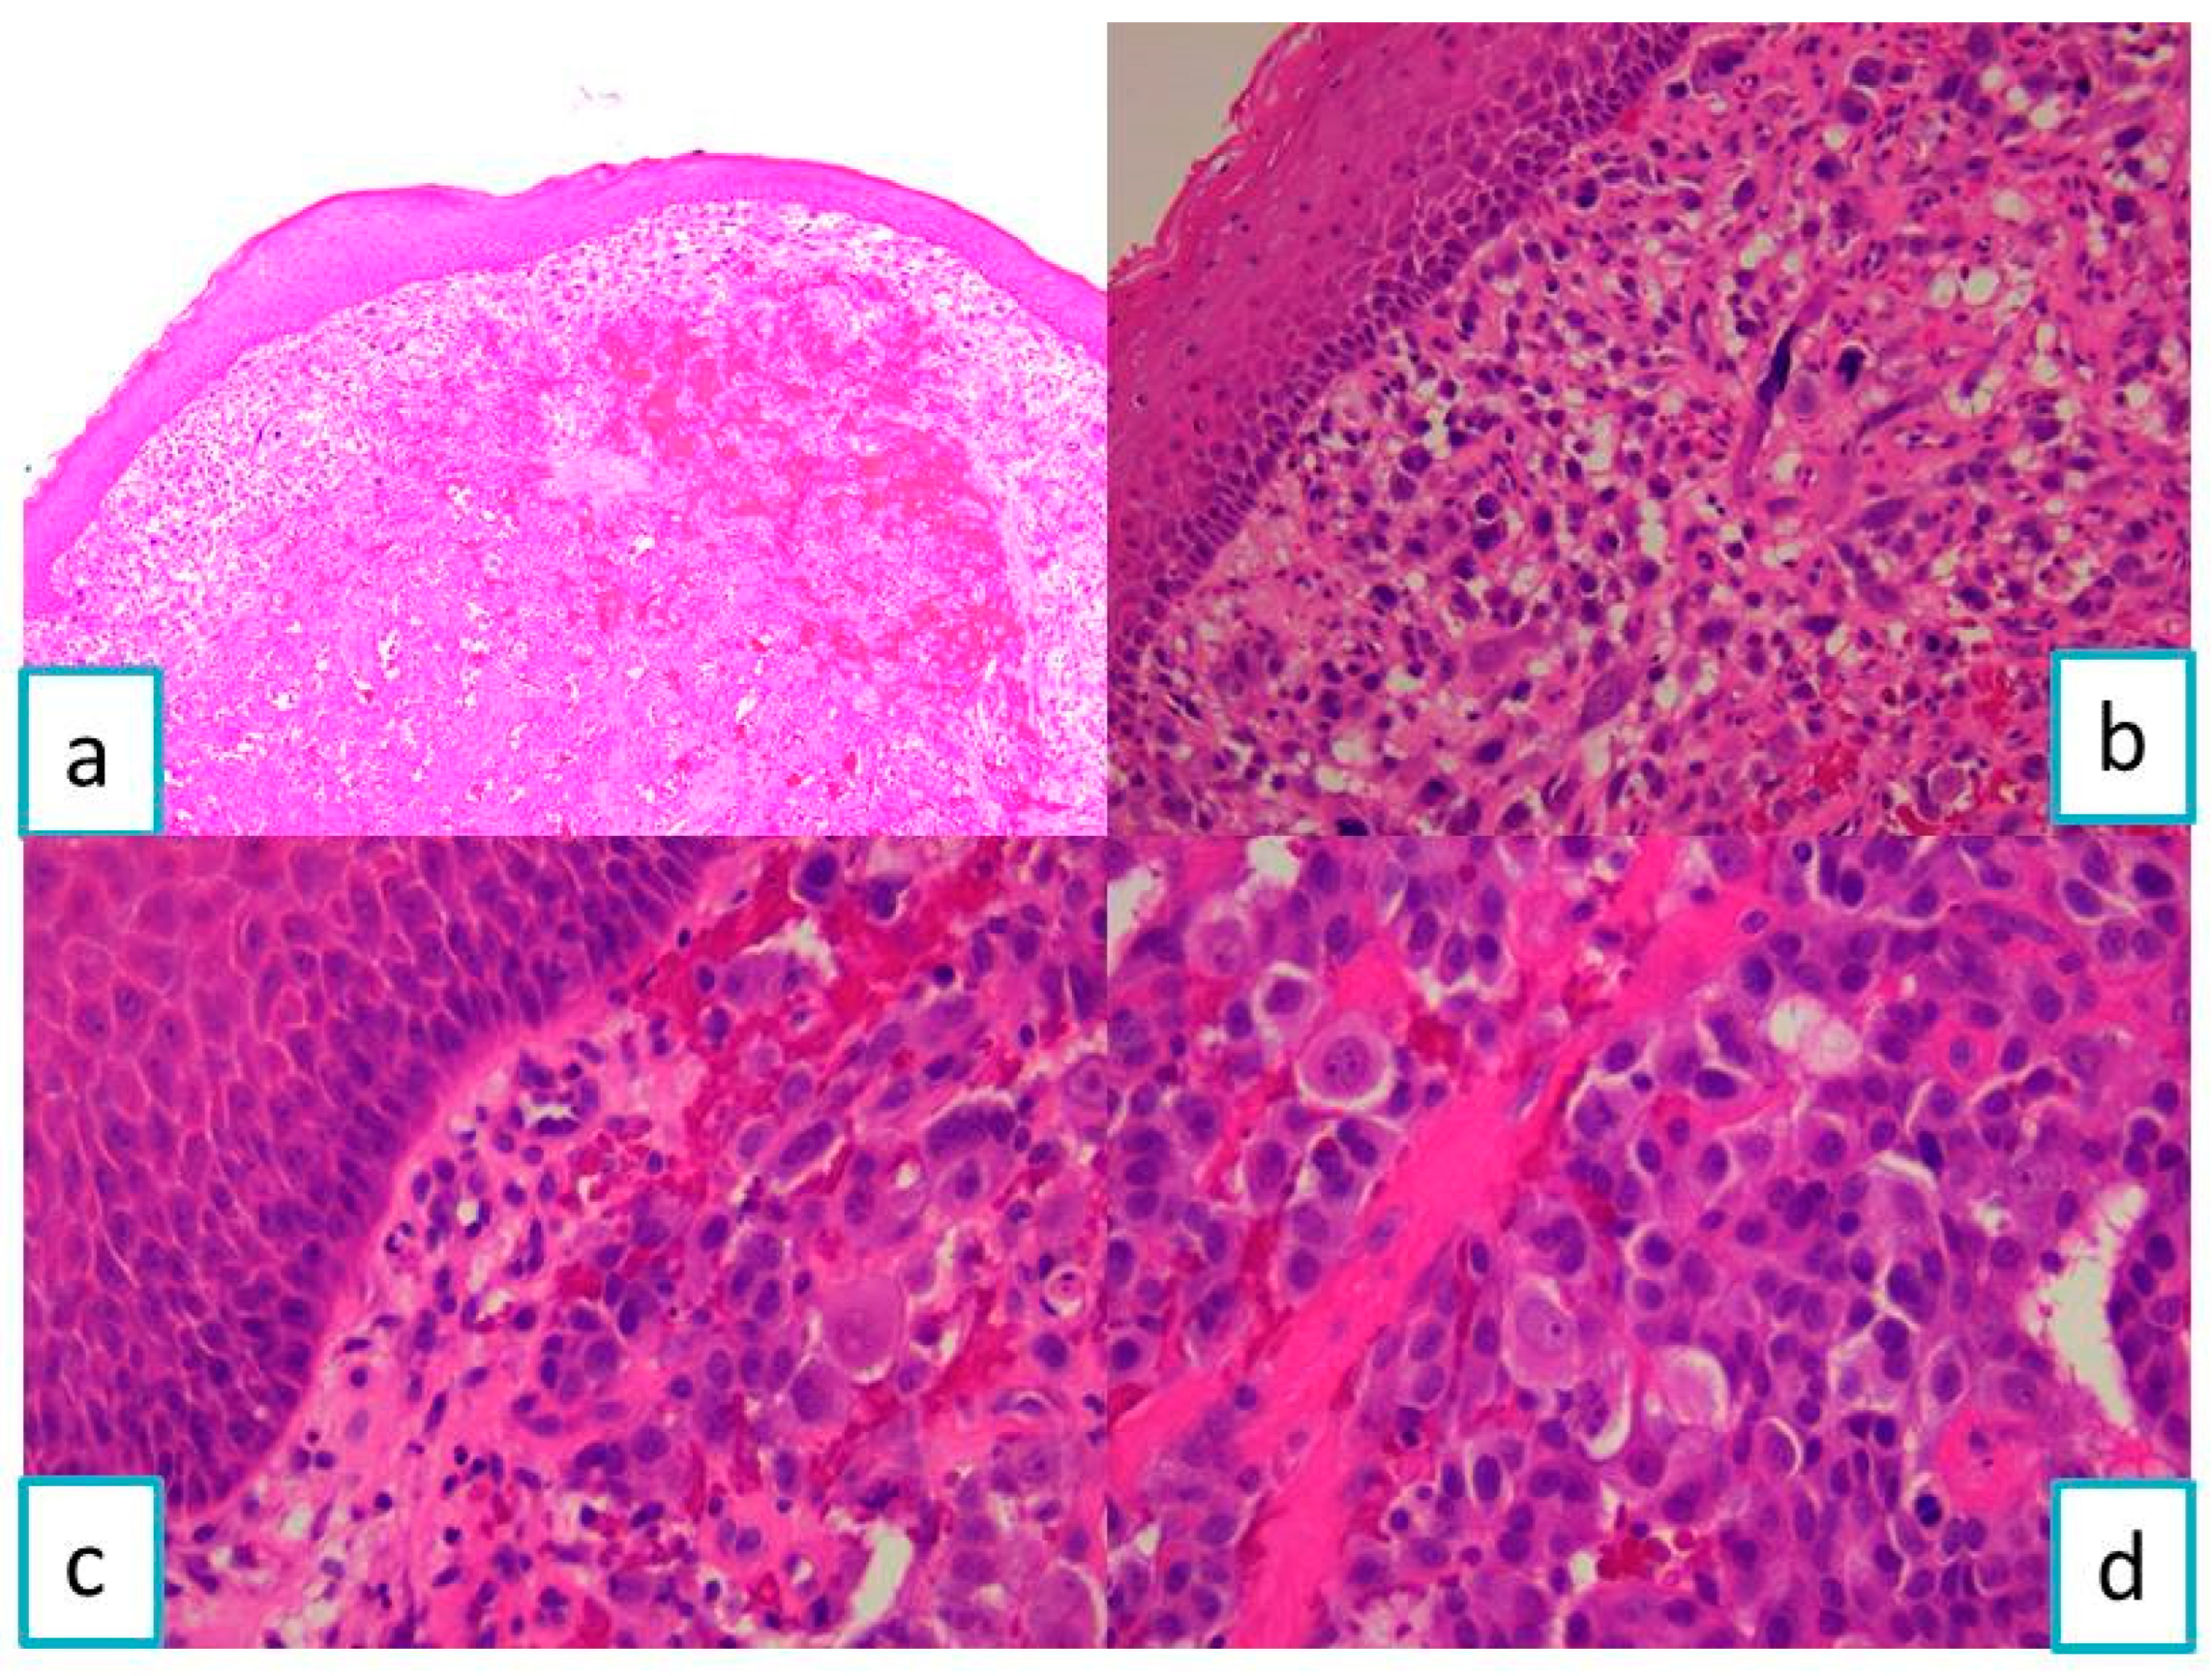

2.1.2. Pathological Findings

2.2.2. Pathological Findings